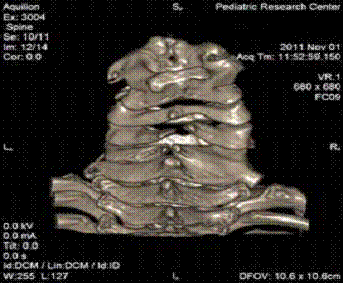

Рис. 1 - Список анатомических образований:

1.Атлант (atlas). 2.Второй шейный позвонок (axis). 3.Остистый отросток

(processus spinossus). 4.Дуга позвонка (arcus vertebrae). 5.Верхний суставной

отросток (processus

articularis

superior). 6. Тело позвонка

(corpus vertebrae).

7. Первый грудной позвонок (vertebra

thoraca I).

8. Затылочная кость (os occipitale). 9. Первое ребро (costa I). 10. Нижний

суставной отросток (processus

inferior). 11. Поперечный

отросток (processus transversus)

Описание

На представленной рентгенограмме в прямой

проекции визуализируются 7 позвонков шейного отдела позвоночного столба. Тело

позвонков представляет собой участки затемнения четырех угольной формы, верхний

и нижний края которых вогнуты. Тень дуги позвонка накладывается на тень его

тела. Тень остистого отростка выглядит в виде интенсивного участка затемнения

овальной формы, накладывается на тень тела и на тень дуги. Поперечные отростки

расположены во фронтальной плоскости, c боку от тела позвонка, их контур

неровный за счет расположенных на нем передних и задних бугорков. Верхние и

нижние суставные отростки ориентированы горизонтально. На рентгенограмме

визуализируются хорошо заметные щель дугоотростчатых суставов, представленные

дугообразными полосами просветления. Шейные позвонки соединяются между собой

при помощи межпозвоночных дисков (discus intervertebrallis), этот участок

представлен полосой просветления расположенной между их телами.

У первого шейного позвонка, который является не

типичным (атлант) на рентгенограмме визуализируются передние и задние дуги

расположены латеральные от них боковые массы.

Второй шейный позвонок (осевой) имеет зуб, тень

которого накладывается на тень передний дуги атланта.

Кроме указанных анатомических образований на

рентгенограмме визуализируется участок затылочной кости, первые две грудные

позвонка, задний отрезок первых двух ребер.

Компьютерную томографию шейного отдела мы

назначаем для лучшей визуализации признаков дисплазии костной ткани, активно

используя возможность 3D-реконструкции (рис. 5).

Рис. 5 - Частичная конкресценция тел позвонков в

сочетании со spina bifida